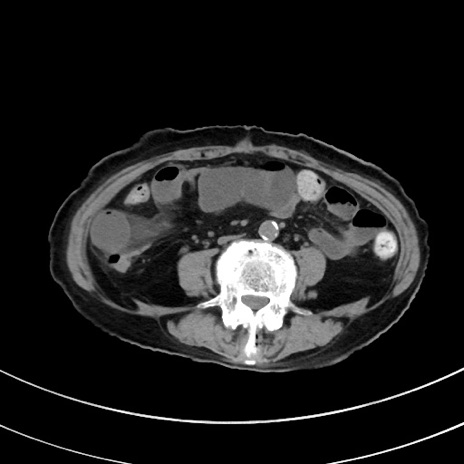

冠状断像

【症例】70歳代 女性

【主訴】心窩部痛

【現病歴】延髄病変の精査・加療にて神経内科入院中。本日より心窩部痛あり。

【既往歴】虫垂炎

【身体所見】右下腹部を中心に圧痛と反跳痛あり。

【データ】WBC 10900、CRP 0.02